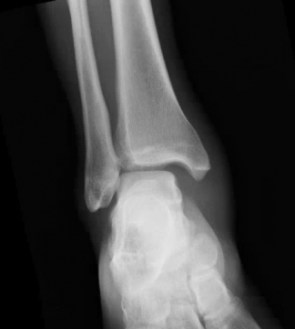

What’s the diagnosis? Gepost op 10 januari 2019 door netwerkvsseh What’s the diagnosis? @emdaily.cooperhealth.org Dit delen: Delen op X (Opent in een nieuw venster) X Share op Facebook (Opent in een nieuw venster) Facebook Delen op LinkedIn (Opent in een nieuw venster) LinkedIn E-mail een link naar een vriend (Opent in een nieuw venster) E-mail Afdrukken (Opent in een nieuw venster) Print Vind-ik-leuk Aan het laden... Gerelateerd